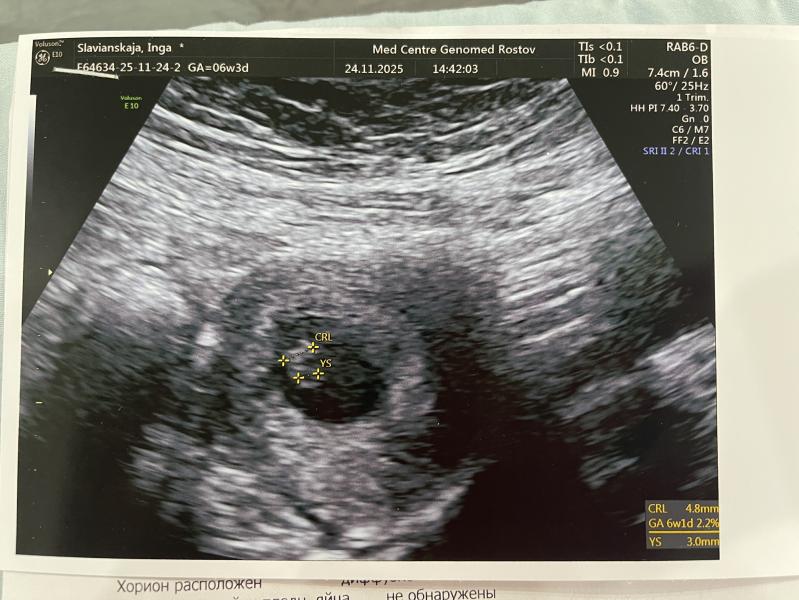

Доброе утро❤️ вчера сходила на узи) помогите разобраться с показателями) жм-3,0 а пя-?4,8? Как теперь дожить до 1скрининга ?!)))